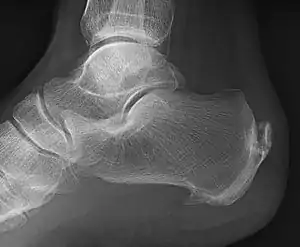

Enthesophyte

An enthesophyte, consisting of calcification deposits within the Achilles tendon at its calcaneal insertion. The Achilles tendon is wider than normal, further suggesting inflammation.

Enthesophytes are abnormal bony projections at the attachment of a tendon or ligament.[1] They are not to be confused with osteophytes, which are abnormal bony projections in joint spaces. Enthesophytes and osteophytes are bone responses for stress.[1]